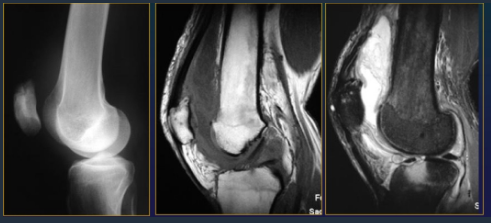

Meniscal tear

Rupture of cruciate ligaments

Periarthrisits, intraarticlar chondromatosis

Knee

Gonarthrosis